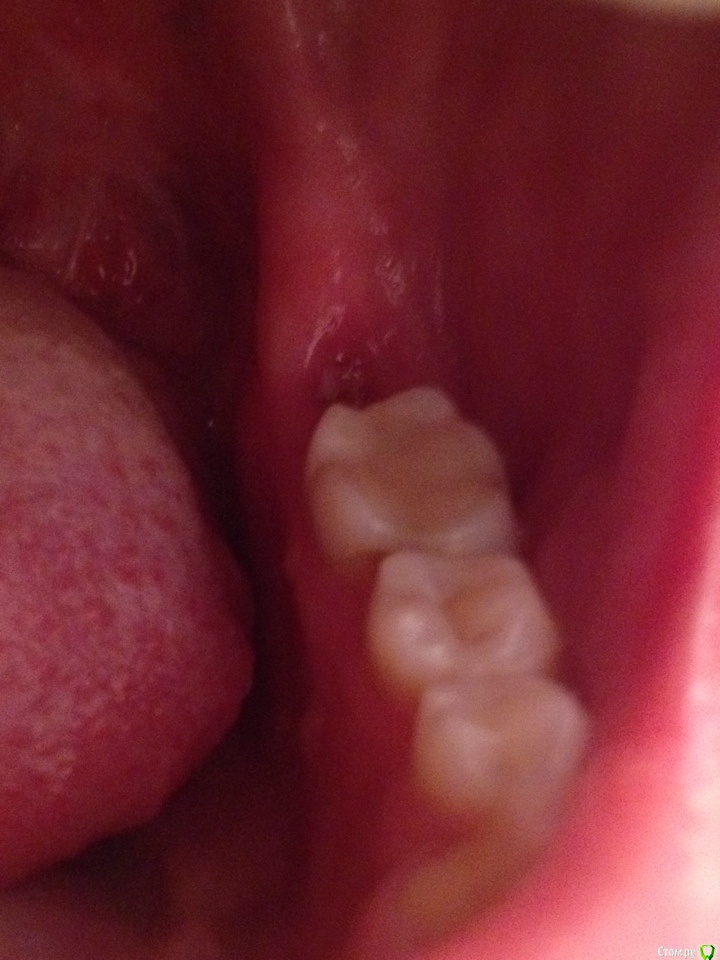

DA89 Опубликовано 12 ноября, 2015 Автор Поделиться Опубликовано 12 ноября, 2015 Нужен снимок после удаления и фото хорошего качества. прицельный37.bmp Ссылка на комментарий

red_butler Опубликовано 12 ноября, 2015 Поделиться Опубликовано 12 ноября, 2015 На снимках все не так уж плохо, но для выбора дальнейшей тактики нужен очный осмотр. Альвеолиты иногда, к счастью редко, носят затяжной характер. Ссылка на комментарий